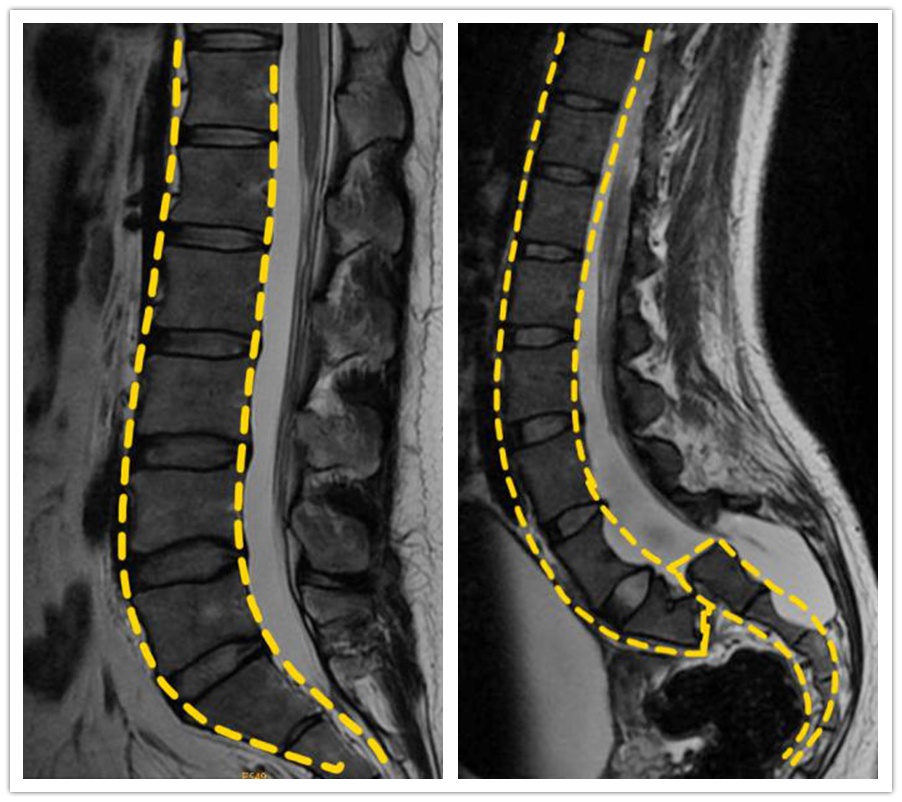

重症 陶惠人教授 腰椎严重滑脱 挽救濒临瘫痪女孩